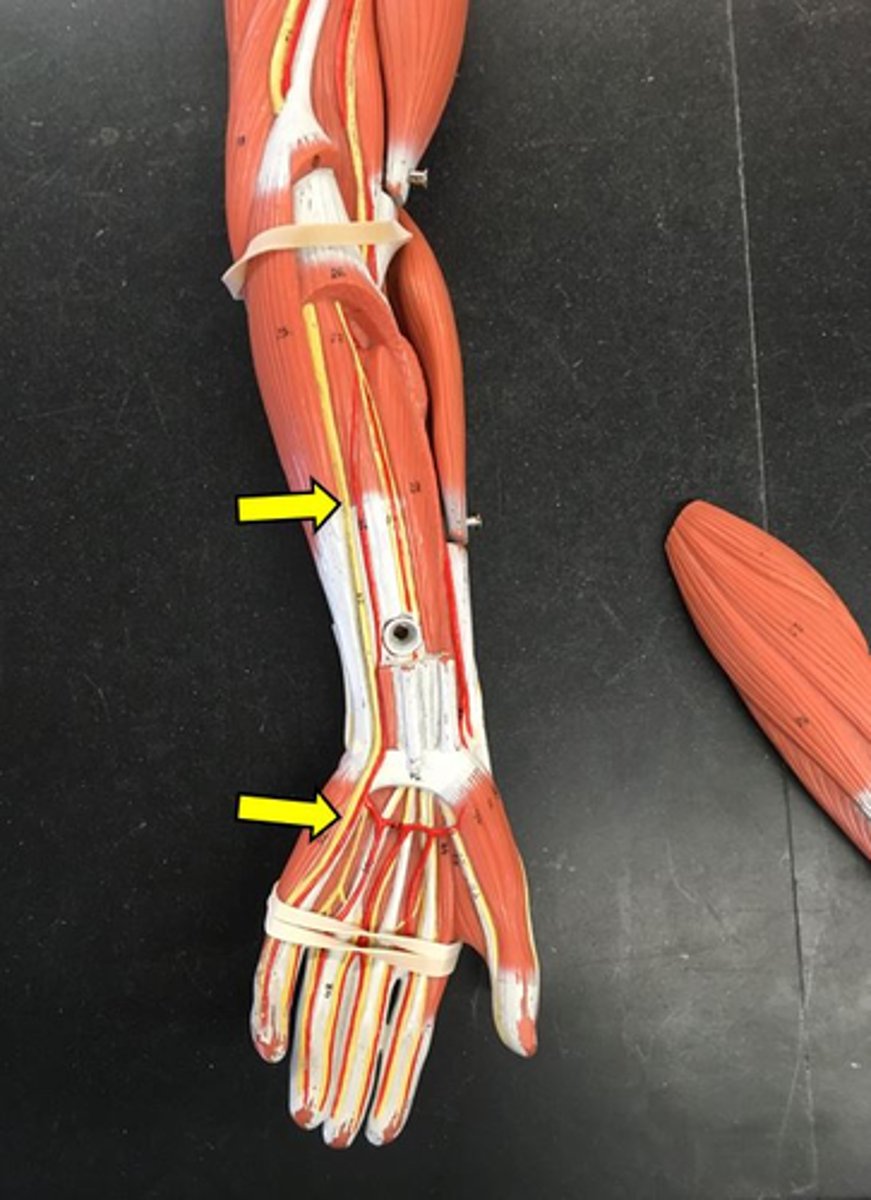

median nerve

ulnar nerve

saphenous nerve

common fibular nerve

tibial nerve